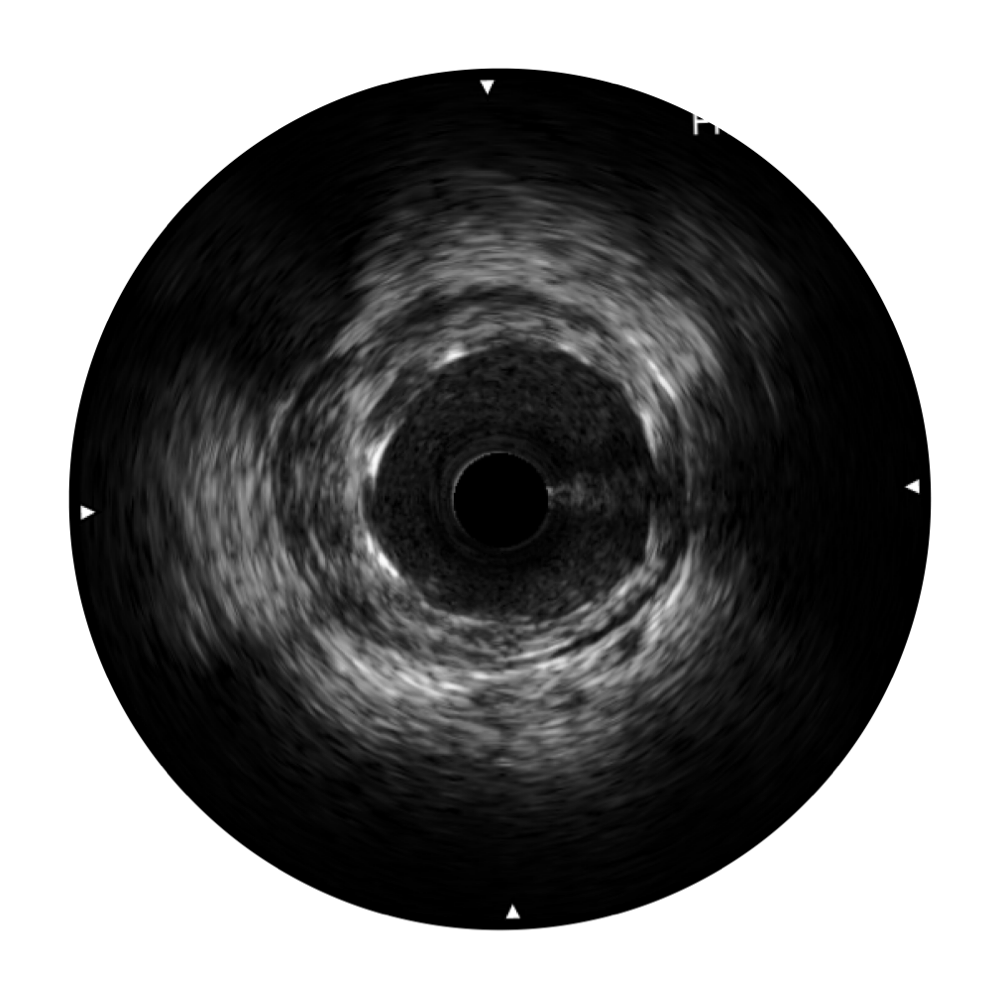

狗万官方网站宽频IVUS图像

传统IVUS图像

对比传统IVUS导管成像,狗万官方网站宽频IVUS图像的近场支架梁显影更细腻,远场中膜外血管仍清晰可辨,兼顾远中近,兼顾分辨力与穿透深度